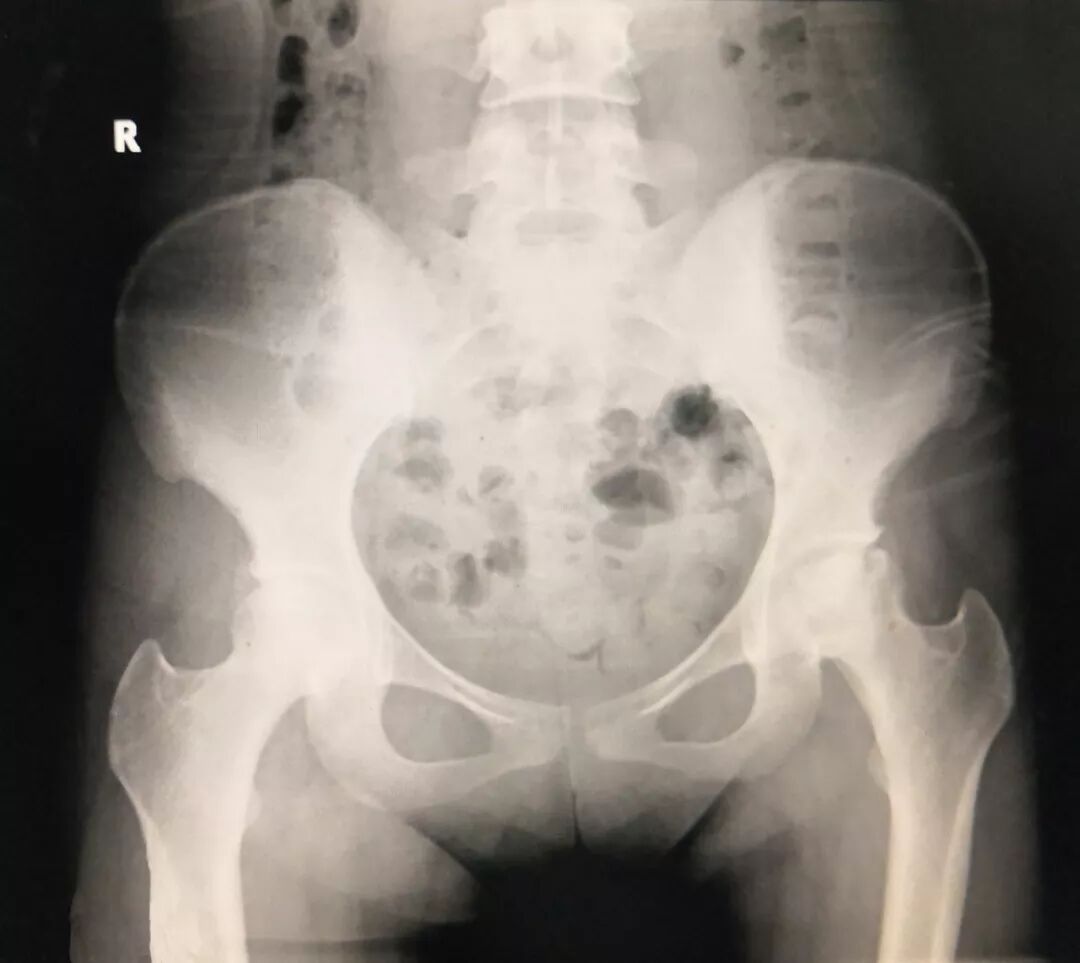

術(shù)前顯示:雙側(cè)股骨頭壞死

術(shù)后右側(cè)鉭棒植入,左側(cè)假體位置良好